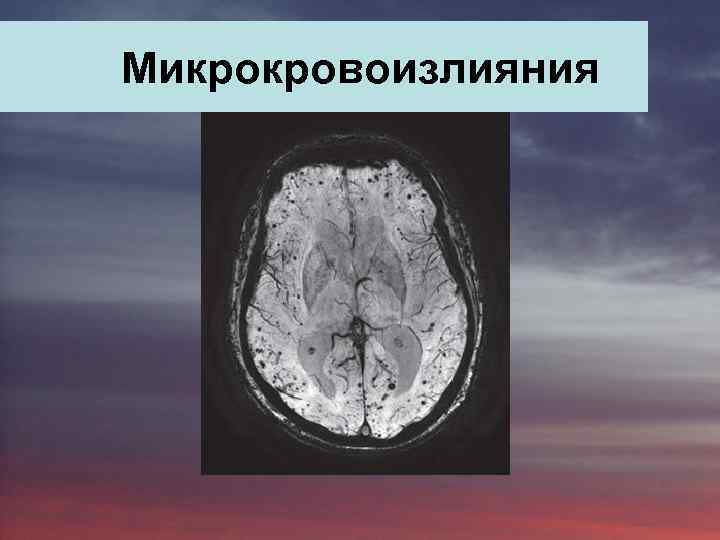

Mикрокровоизлияния